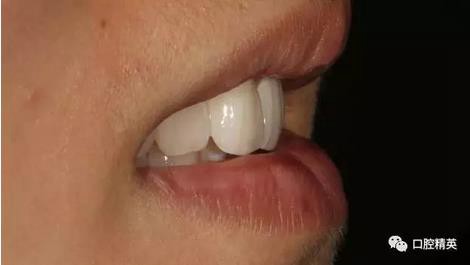

口內(nèi)正側(cè)位及切端特寫

從側(cè)位照可看出遠(yuǎn)中切角略有回收